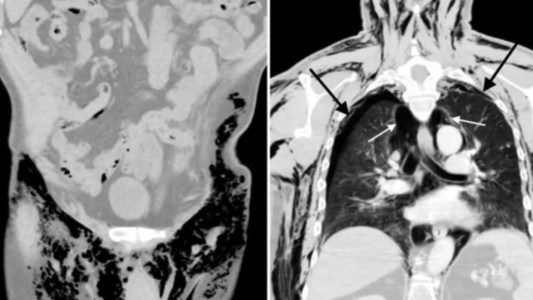

China registró un primer caso de viruela del mono en Chongqing